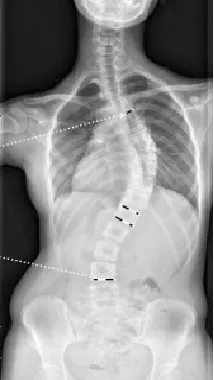

▷特发性脊柱侧凸

特发性脊柱侧凸是所有脊柱侧凸中最多见的,原因不明。其中青少年特发性脊柱侧凸(AIS)最常见,发病率1.5%-3%,占全部脊柱侧凸的75%-80%。约80%的AIS患者需佩戴支具以控制侧凸进展,佩戴支具的患者中,约1/4最终需要手术治疗。

▲ 女,12岁,特发性脊柱侧凸、先天性脊柱畸形